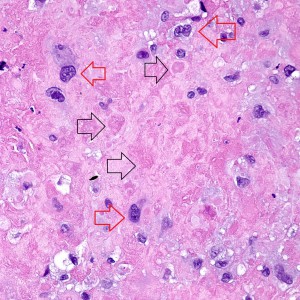

On higher power, we can see that this nodule is mostly composed of this pink amorphous material with interspersed large, round cells with abundant eosinophilic and sometimes clear cytoplasm (arrows). There are essentially no mitoses and atypia is not very prominent.

On higher power of the acellular areas we can see vague outlines of the cells that may have been there and have now degenerated into this hyalinized stroma (black arrows). The cells that remain are large, round to oval, with dense eosinophilic to clear cytoplasm (red arrows).